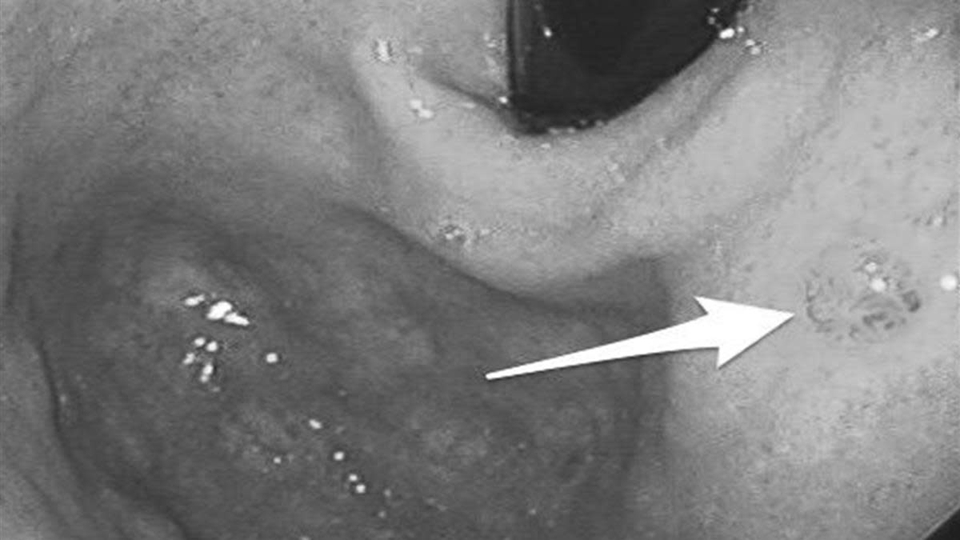

Cơ chế này chịu tác động của nhiều yếu tố. Nhiễm vi khuẩn Helicobacter pylori (HP), ăn mặn kéo dài hoặc thói quen sinh hoạt thất thường đều có thể làm suy yếu lớp bảo vệ niêm mạc dạ dày. Khi quá trình tổn thương và sửa chữa lặp lại nhiều lần nhưng không hoàn chỉnh, niêm mạc có thể xuất hiện “chuyển sản ruột” - một dạng tổn thương tiền ung thư.

Đối với người trên 40 tuổi hoặc có triệu chứng kéo dài, nội soi dạ dày định kỳ là phương pháp quan trọng giúp phát hiện sớm bất thường. Ngoài ra, chế độ dinh dưỡng đầy đủ protein, rau xanh cũng góp phần hỗ trợ phục hồi niêm mạc và ổn định chức năng tiêu hóa.